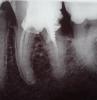

Иоанн Опубликовано 4 июня, 2012 Поделиться Опубликовано 4 июня, 2012 Добрый день! Собираюсь лечить мертвый зуб (нижняя 6-ка) и не могу понять, требуется ли перепломбировка каналов. Зуб лечили около 10 лет назад, стоит металлический штифт и на нем пломба. С тех пор он сильно разрушился у основания, вблизи десны, застревает пища. В платной клинике, куда я хожу несколько лет, мне сказали, что требуется удаление штифта, перебломбировка каналов, а дальше вкладка и коронка. Лечение получается дорогим и довольно долгим. В стоматологической поликлинике мне предложили просто запломбировать кариес и ставить коронку. На вопрос о каналах ответили, что особой необходимости в перепломбировке нет.Как лучше поступить? Два года назад в похожей ситуации я уже ставил коронки на мертвые зубы без перепломбировки. Стоят отлично, не беспокоят. Ссылка на комментарий

dok1 Опубликовано 4 июня, 2012 Поделиться Опубликовано 4 июня, 2012 Перепломбировка в вашем случае желательна. Но ситуация не патовая - нет изменений на верхушках.коронка обязательна. проконсультируйтесь ещё и насчёт пятого зуба. А цена вопроса - вещь обстрактная, в себя же инвестируете. Ссылка на комментарий

ger_berra Опубликовано 4 июня, 2012 Поделиться Опубликовано 4 июня, 2012 Оюязательно перелечивать,если от зуба ещё что-то осталось.Очень смущает дистальный дефект. Ссылка на комментарий